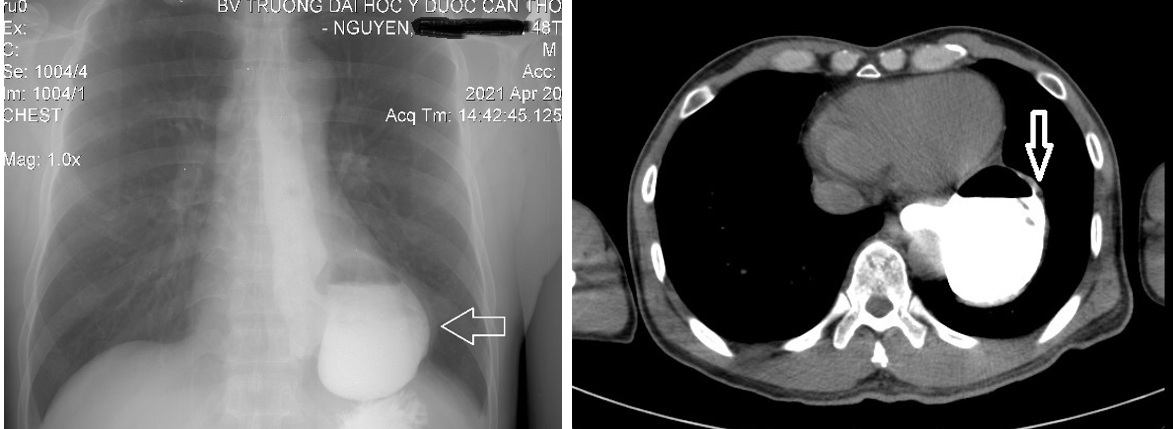

1. Trường hợp thứ nhất: Bệnh nhân nam, 48 tuổi vào Bệnh viện Trường Đại học Y Dược Cần Thơ vì khó nuốt, cách nhập viện khoảng 1 năm, bệnh nhân cảm thấy khó nuốt với thức ăn đặc, cảm giác khó chịu sau xương ức, thỉnh thoảng có ợ nóng và nôn ra thức ăn. Cách nhập viện # 3 tháng, bệnh nhân cảm giác nuốt nghẹn với thức ăn lỏng, nước, cảm giác khó tiêu, ợ hơi nhiều sau ăn, đôi khi có ho khan, sụt cân # 2-3 kg/năm. Không có yếu tố tăng nặng hoặc giảm nhẹ cụ thể, khám sức khỏe không phát hiện bất thường. Chỉ số BMI của bệnh nhân trong giới hạn bình thường. Khi khám, thấy bụng mềm nhưng có cảm giác đau vừa phải ở thượng vị. Điện tâm đồ, siêu âm tim và chụp X-quang phổi của bệnh nhân đều bình thường. Vì vậy, các nguyên nhân tim và phổi đã được loại trừ. Các xét nghiệm của bệnh nhân bao gồm xét nghiệm máu thường quy, sinh hóa và siêu âm ổ bụng chưa ghi nhận bất thường. X-quang thực quản-dạ dày có uống thuốc cản quang: túi thừa thực quản 1/3 dưới. MSCT ngực: Túi thừa thực quản 1/3 dưới, tổn thương mô kẽ và xơ đỉnh phổi (P) nghĩ tổn thương cũ

Hình 1: Túi thừa thực quản 1/3 dưới thực quản trên X-quang thực quản – dạ dày có cản quang, và trên MSCT ngực (mũi tên trắng)